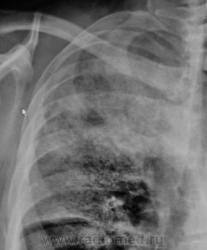

Томограммы.

По прямой рентгенограмме в больших сомнениях пребывал - сомнения по поводу абсцедирования...

А, я, наверно поспешил, абсцедирование в протокол забацал.